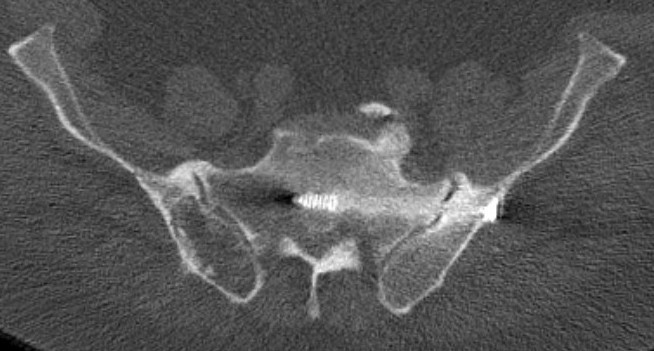

Sacro-iliac screws

Technique

Radiolucent table with image intensifier

- 45o cephalad and caudal / inlet and outlet views

Must reduce SI joint

- reduce vertically with traction on limb / outlet view

- reduce AP usually via anterior plate or external fixation / inlet view

Guide wire insertion into body of S1

- anatomic safe zone

- between S1 foramen and superior ala on outlet view (outlet view)

- between neural canal and anterior body (inlet view)

Insert 6.5 mm partially threaded cannulated screw, to aid compression

Post operative

Check screw position with CT

Protected weight bear for six weeks